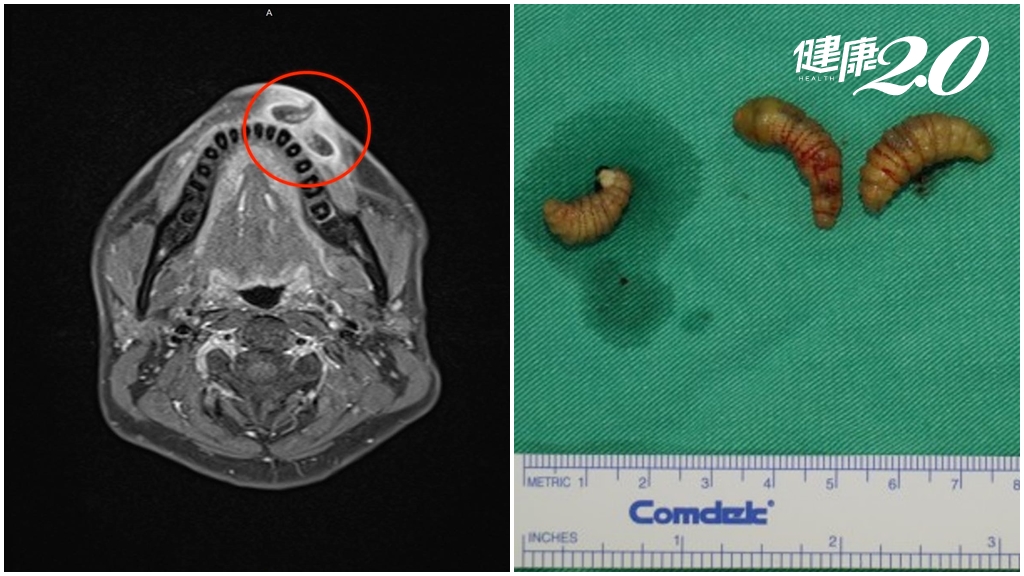

▲患者影像學檢查發現蟲跡(左圖),手術取出3隻馬蠅幼蟲(右圖)。(馬偕醫院提供)

陳先生在門診檢查後,發現嘴唇有3個傷口持續滲液,且隱隱約約看得到有物體活動跡象,因嘴唇周圍有大血管,蟲體為躲避,容易碰撞造成出血,曾在門診嘗試夾出,但因病人無法忍受,溝通治療方式後,為求謹慎,選擇全身麻醉,以便順利「活捉蟲蟲」。手術時間約15分鐘,成功活捉3隻嘴唇上的寄生蟲,取出後的蟲體分別送病理檢驗及台大昆蟲系系統分類研究室,由蕭旭峰教授鑑別,確認是台灣少見的馬蠅幼蟲。

劉崇基表示,手術時發現,陳先生上嘴唇有1破洞、下嘴唇有2破洞,這3個洞分別是3隻小蟲的窩。每隻蟲體大約1公分寬、2.5公分長,因為蟲卵長大約需2周時間,所以陳先生是等到回國後才有症狀,如果沒把蟲抓出來,可能蟲體成熟後會變成馬蠅從嘴唇內飛出來。